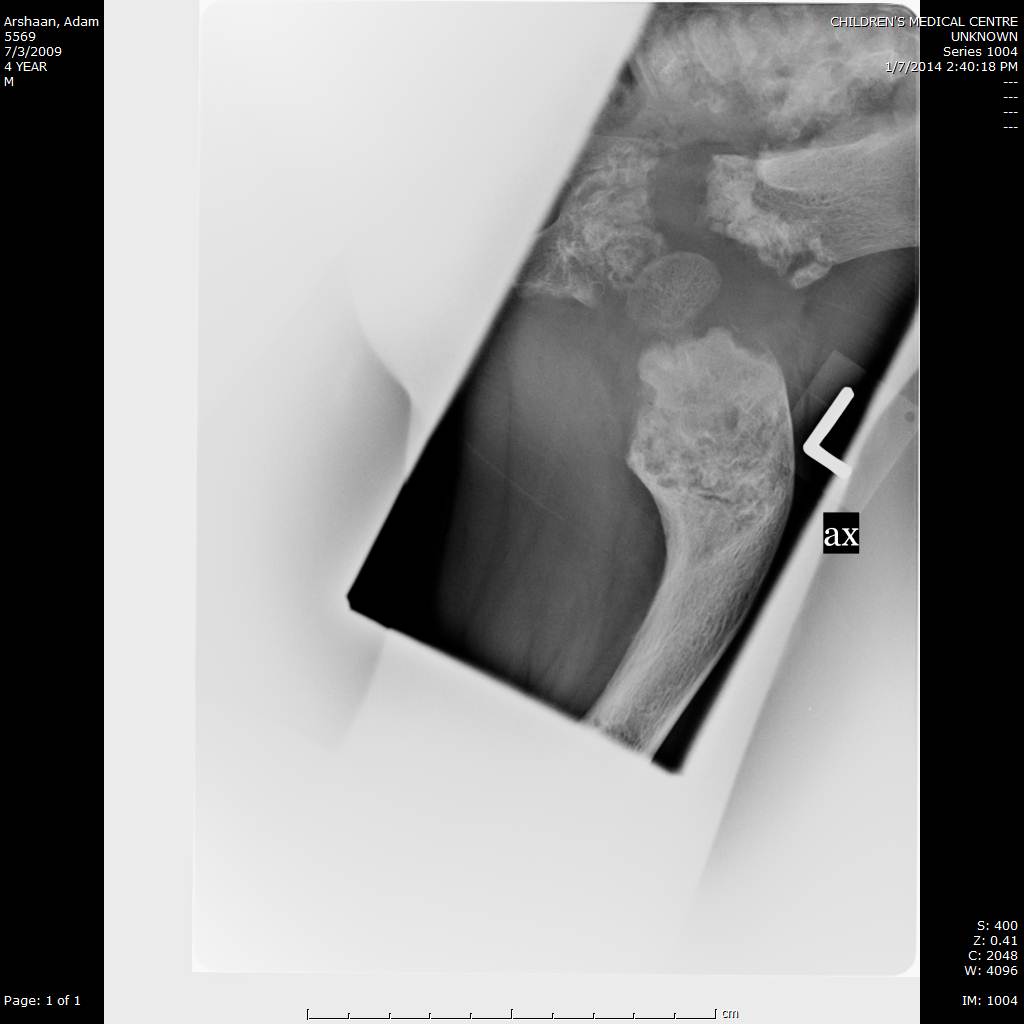

Here we share radiographic images to help with diagnosis of Jansen's disease:

Jansen's patients show extreme disorganization of the metaphyses of the long bones and of the metacarpal and metatarsal bones in sharp contrast to the almost normal appearance of the epiphyseal centers, which on x-ray appear widely separated from the long bones. The chin is receding. The fingers, especially the distal phalanges, are very short. The spine, pelvis, and lower legs are distorted.